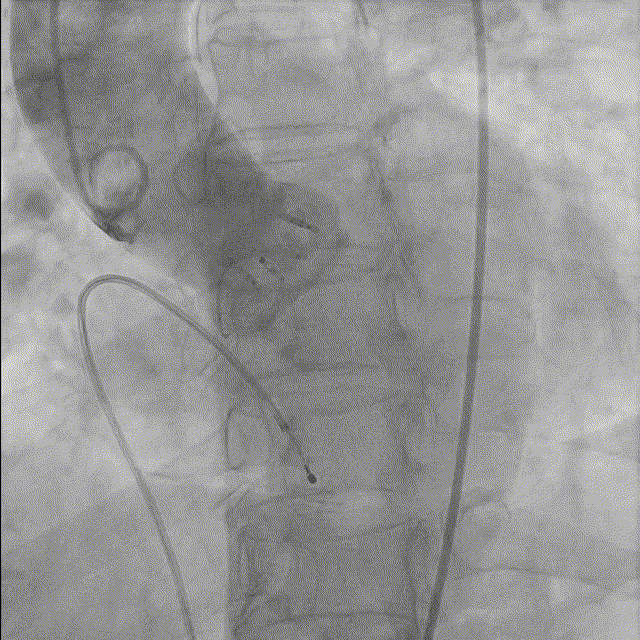

10. 最终造影瓣膜位置理想,无反流,微量瓣周漏。

总结

此次微创介入手术是阜外医院吴永健教授TAVR团队再次采用完全局麻无镇静的极简术式完成Silara主动脉瓣膜治疗重度主动脉瓣狭窄患者。随着手术成功实施, 中国Silara主动脉瓣膜FIM研究入组也顺利结束。中国Silara主动脉瓣膜FIM研究的宝贵经验将为后续确证性临床的顺利开展奠定坚实的基础。相信Silara 主动脉瓣膜将造福更多的主动脉瓣疾病患者!